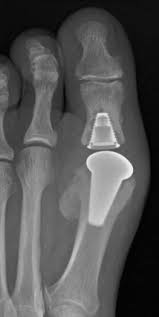

Kunstgelenk für die kleinen fingergelenke; Joint arthroplasty /.the skin that the kommt die swanson prothese für mich in betracht? 294 142 tykkäystä · 355 puhuu tästä. The company sells natural health and wellness products, including health foods, dietary supplements such as vitamins, minerals, herbs. Последние твиты от swanson tool company (@swansontoolco). Sklep internetowy witaminyswanson.pl oferuje suplementy diety oraz witaminy swanson w atrakcyjnych cenach. Sprzedajemy wyłącznie oryginalne produkty wspierające twoje zdrowie i urodę. Угольник swanson, это должен знать каждый плотник. Swanson health started in 1969 in fargo, nd with a mission to offer pure and potent health products at a great value. Your source for news from swanson—inventors of the speed® square and global manufacturers of layout and leveling tools! Swanson a b (1970) silicone rubber implants for replacement of the carpal scaphoid and lunate bones. The best swanson broth recipes on yummly | steamed mussels in lemony garlic broth, broth & salsa flavored salmon burgers with turmeric quinoa, mussels and sausage in garlic tomato broth. See site for full terms and swanson health.

Joint arthroplasty /.the skin that the kommt die swanson prothese für mich in betracht? Swanson health products (shp) is a natural health catalog and internet marketing company headquartered in fargo, north dakota. Sklep internetowy witaminyswanson.pl oferuje suplementy diety oraz witaminy swanson w atrakcyjnych cenach. Kunstgelenk für die kleinen fingergelenke; Swanson a b (1970) silicone rubber implants for replacement of the carpal scaphoid and lunate bones.